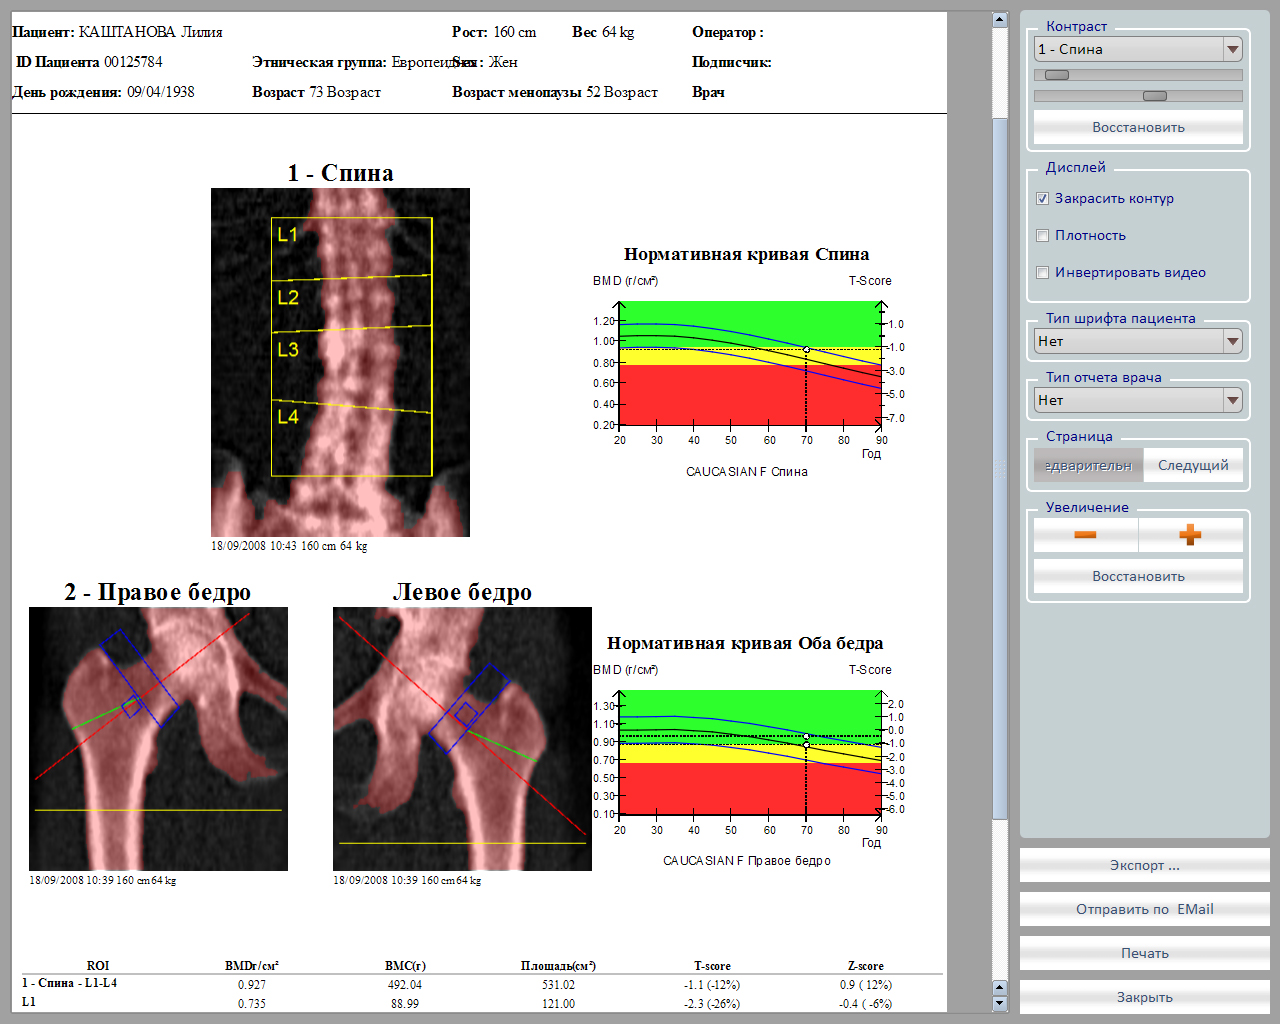

Главной особенностью аппарата является широкий спектр возможных исследований: поясничный отдел позвоночника, проксимальный отдел бедренной кости, кость предплечья, обследование позвоночника в боковой проекции, боковая проекция оценки позвонков, возможность проводить исследования состава тела.

- Автоматический расчет: плотности шейки бедра, вертела бедра, позвоночника, предплечья и треугольника Вордса

- Цветная распечатка отчета: (плотность кости + опорный график)

- Оценка: предполагаемой стадии остеопороза

- Оценка: риска перелома